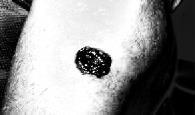

Inputskincancerimage

Figure 4 and figure 5 shows the feature extracted done with magnitude and real part of gabor filter. The classification operation is done and it indicates the Basel cell carcinoma classification. The metric for analysis of performanceofSVMareasfollows.

Processedskincancerimage